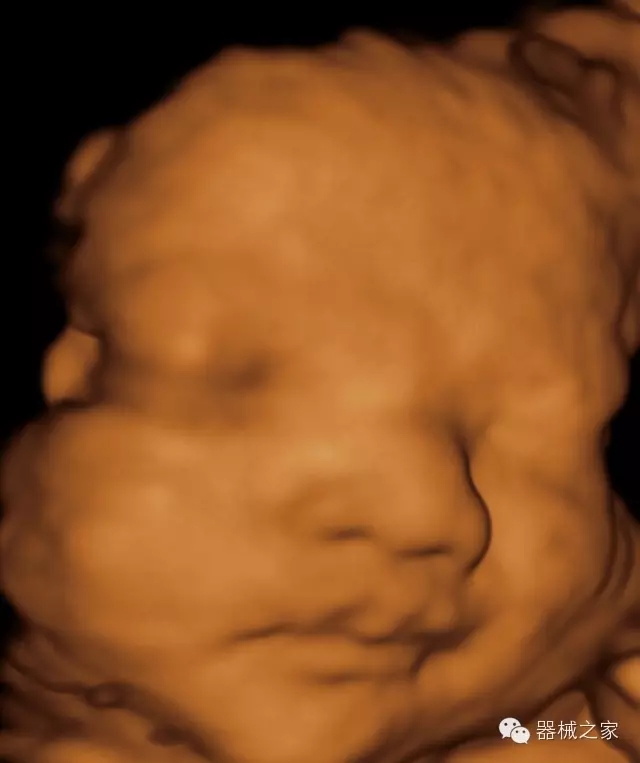

臨床圖片賞析

產(chǎn)品特點(diǎn)

·獨(dú)有的RF平臺提高微小細(xì)節(jié)顯示、圖像對比度和邊界清晰度;

·特有的XCEN探頭,超寬的帶寬,表現(xiàn)更高分辨率和對比度;

·單晶純凈波探頭提供更佳的穿透力和彩色敏感度;

·完整的3D/4D臨床應(yīng)用,STIC, MCUT 和Auto NT等滿足產(chǎn)科所有應(yīng)用;

·更高的HQ羊膜腔鏡成像技術(shù)精細(xì)觀察每一個(gè)暗區(qū)細(xì)節(jié);

·智能的觸摸屏界面,能任意角度方位旋轉(zhuǎn)3D圖像,以及注釋快速標(biāo)記,提供直觀與便捷的操作,提高了工作效率;

·Needle Enhancement 穿刺增強(qiáng)技術(shù),清晰顯示穿刺針尖,定位目標(biāo)精確穿刺;

·智能的聲控功能,以及全屏顯示真正意義上解決醫(yī)生術(shù)中應(yīng)用;

·獨(dú)有的Xcen高頻18MHz探頭,使微小病灶的顯示成為現(xiàn)實(shí),為臨床提供了更廣泛的臨床應(yīng)用;

·Xcen超寬頻帶探頭技術(shù)比常規(guī)探頭頻寬提高了30%,具有更廣泛的臨床應(yīng)用,更高的頻率讓我們獲得了更好的細(xì)微分辨率和對比度的圖像;

·智能感知組織特異性的VTissue技術(shù),結(jié)合特有高達(dá)22MHzXcen線陣探頭, 以及獨(dú)有敏感的RF射頻血流提供了優(yōu)異臨床圖像;

·智能的教學(xué)操作流程提供全面及專業(yè)的操作步驟指導(dǎo),便捷藍(lán)牙傳輸保障信息流暢;

·藍(lán)牙傳輸/ WIFI 郵件/ 移動(dòng)網(wǎng)絡(luò)/ DICOM;

·飛依諾特有心臟純凈波探頭提供更好的穿透力和彩色敏感度,以及結(jié)合TView梯形拓展改善困難病人深部組織成像;

·獨(dú)有RF敏感血流使得心臟血流完美呈現(xiàn);

CFDA注冊證編號

·國械注準(zhǔn)20152231021